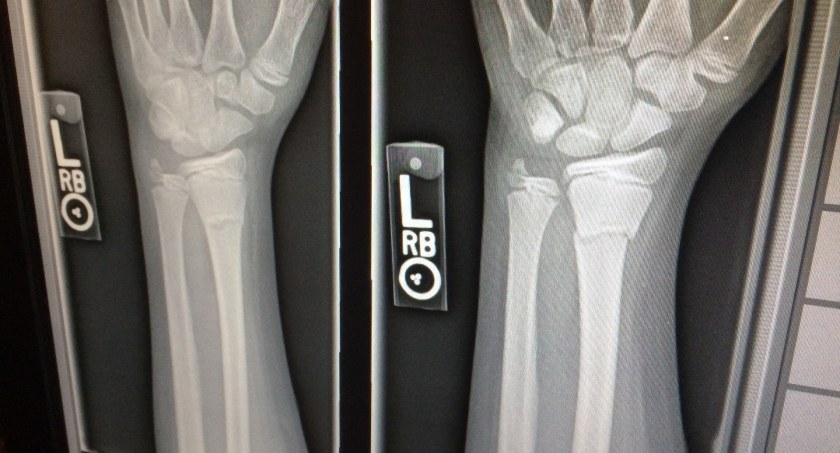

Święta ze złamaną ręką. O leczeniu: „To koszmar, którego już nie chcę więcej